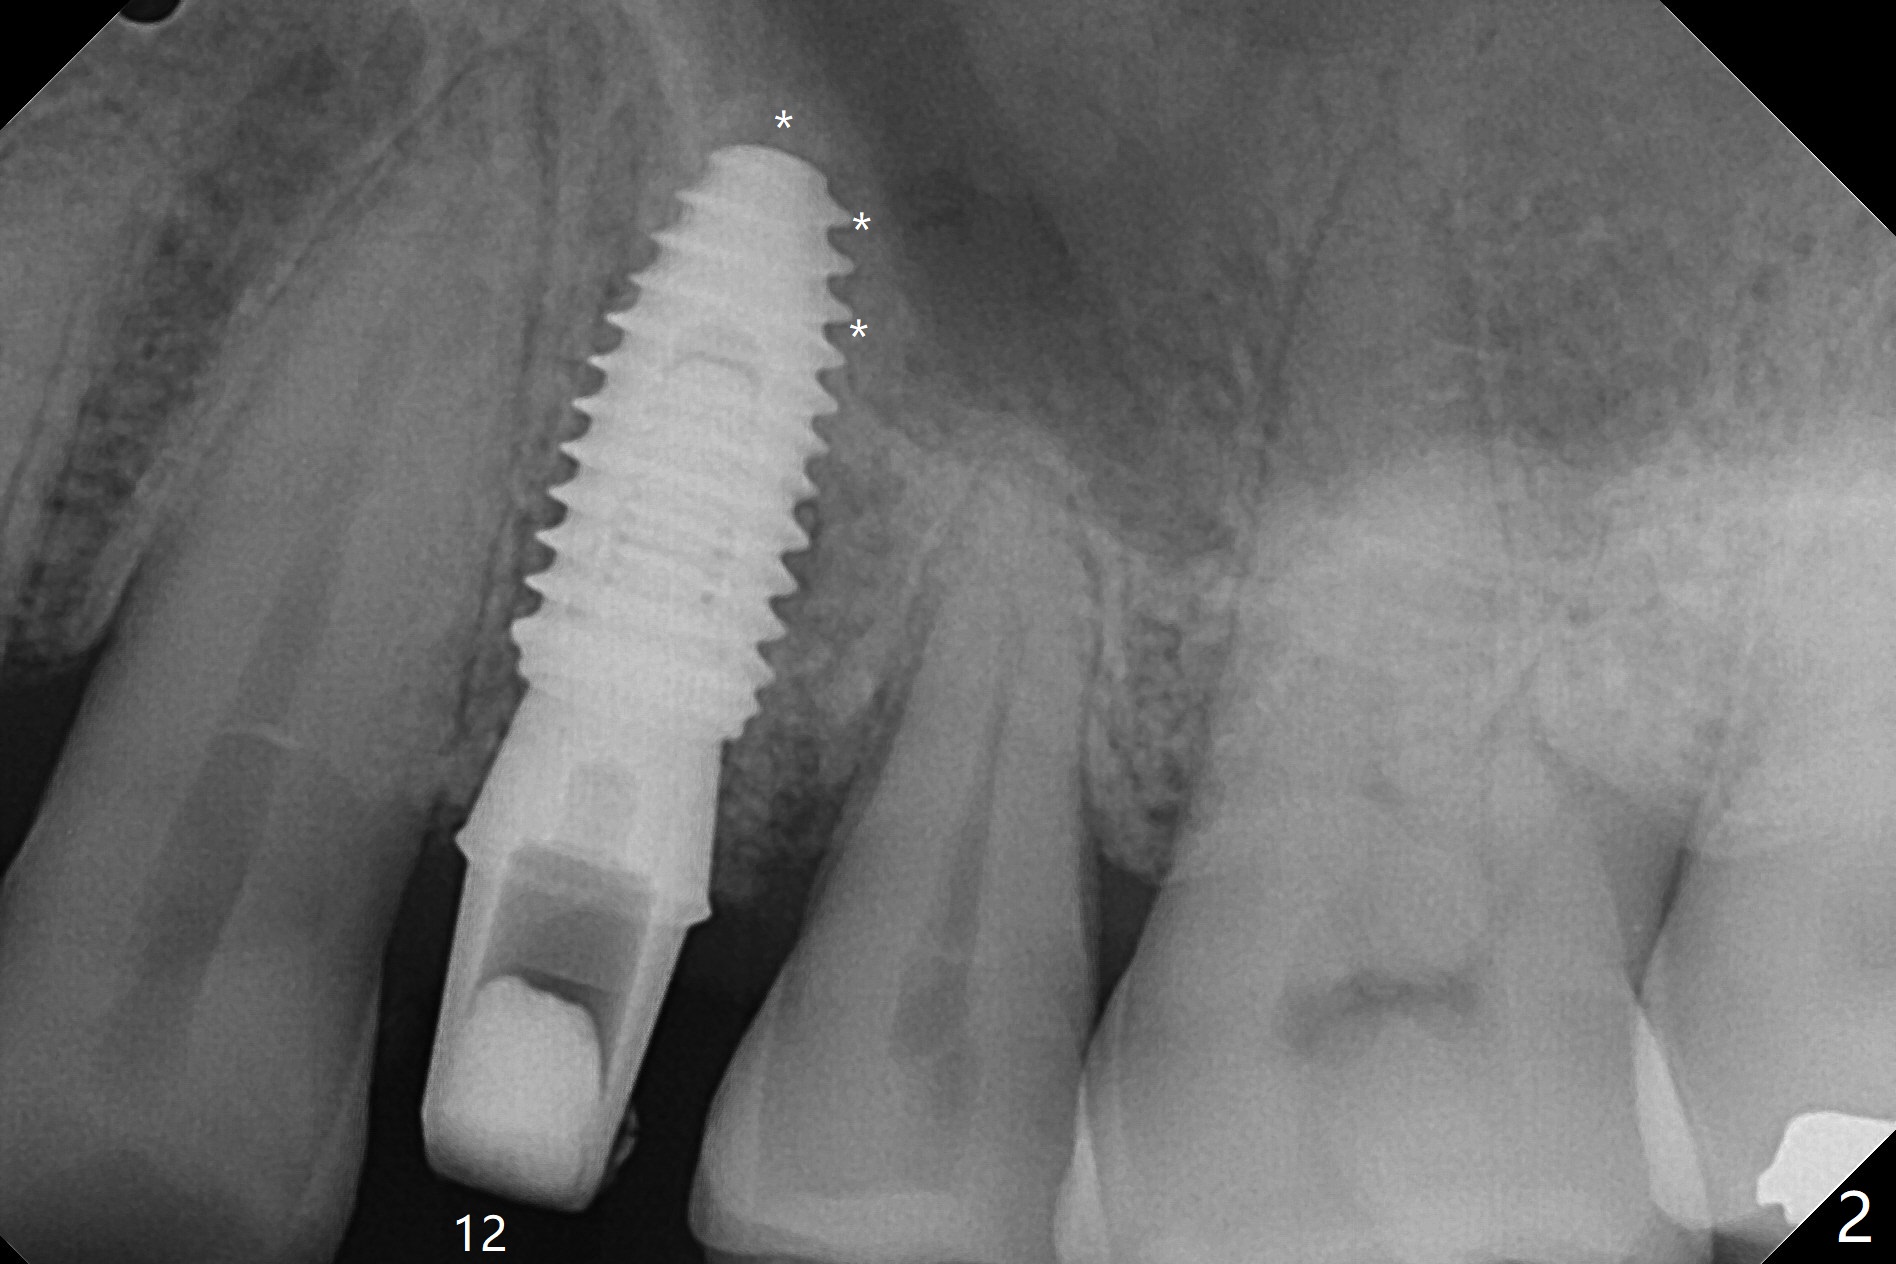

In fact the designed initial drills do not get to the bone with guides. After use of the next length drills (1.5 mm longer with sharp end), the sinus floor perforates without membrane perforation. Once 3.5 mm drill is used following sequential osteotomy, a 4x10 mm dummy implant is placed for sinus lift with 1 mm short of the depth and >50 Ncm. Following the dummy implant removal, allograft in the amount of 2 to 3 amalgam carriers is delivered for sinus lift (Fig.1,2 white *), followed by implant placement (4.5x10 mm, >55 Ncm). More allograft is placed before and after abutment insertion (black *). As usual, an immediate provisional is fabricated at each site. After removal and cleaning, the abutments are reseated and retorqued to 30 Ncm 11 months postop (Fig.3,4). Sinus lift is indistinct 15 months postop (Fig.5,6), probably due to radiation overexposure, although placement trajectory is good.